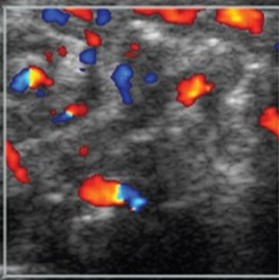

| Hyperemia by colour Doppler | |

| Strengths | Considerations |

|

![]() ![]() |

First: Normal intestinal image shows 3- to 9-colour speckled pattern indicating normal perfusion Second: Hyperemia with a Y pattern |